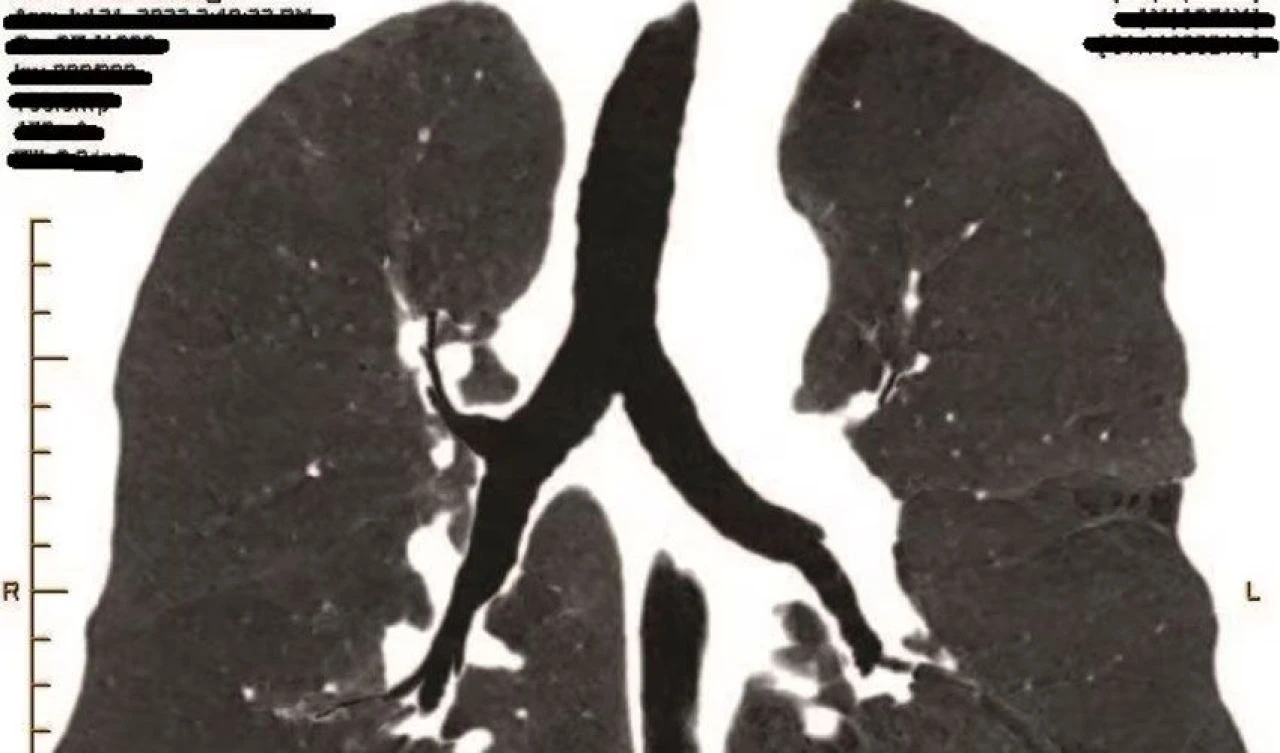

Avustralya'daki bir kömür madeninde çalışan Craig Keogh, 'pnömokonyoz' olarak bilinen solunum yolu hastalığına yakalandı. Şirkete dava açan Craig, işverenin ihmali olduğunu belirtti. Bir daha asla çalışamayacağı söylenen Craig, mahkemede dönüm noktası niteliğinde bir hukuki zafer ve milyonlarca dolarlık tazminat kazandı.

Madende makine operatörü olarak görev alan Craig Keogh, "pnömokonyoz" davasını kazanan ilk Avustralyalı oldu. Bu dava, diğer mağdurların da başarılı tazminat taleplerinde bulunmalarının önünü açtı.

2018'den beri ruh sağlığı sorunlarıyla mücadele eden Keogh, madenden çıkan tozun neden olabileceği tehlikeler konusunda hiç uyarılmadığını ve iş yerinde hiç maske takmadığını söyledi.

Yargıç David Russell, Keogh'un solunum ve psikiyatrik sağlığının bir daha asla çalışamayacağı anlamına geldiğine ve kanıtların solunum durumunun kötüleşeceğini gösterdiğine ikna oldu. Kararın aynı durumdaki kömür madencilerinin tazminat almalarında güçlü bir emsal teşkil edeceği düşünülüyor.